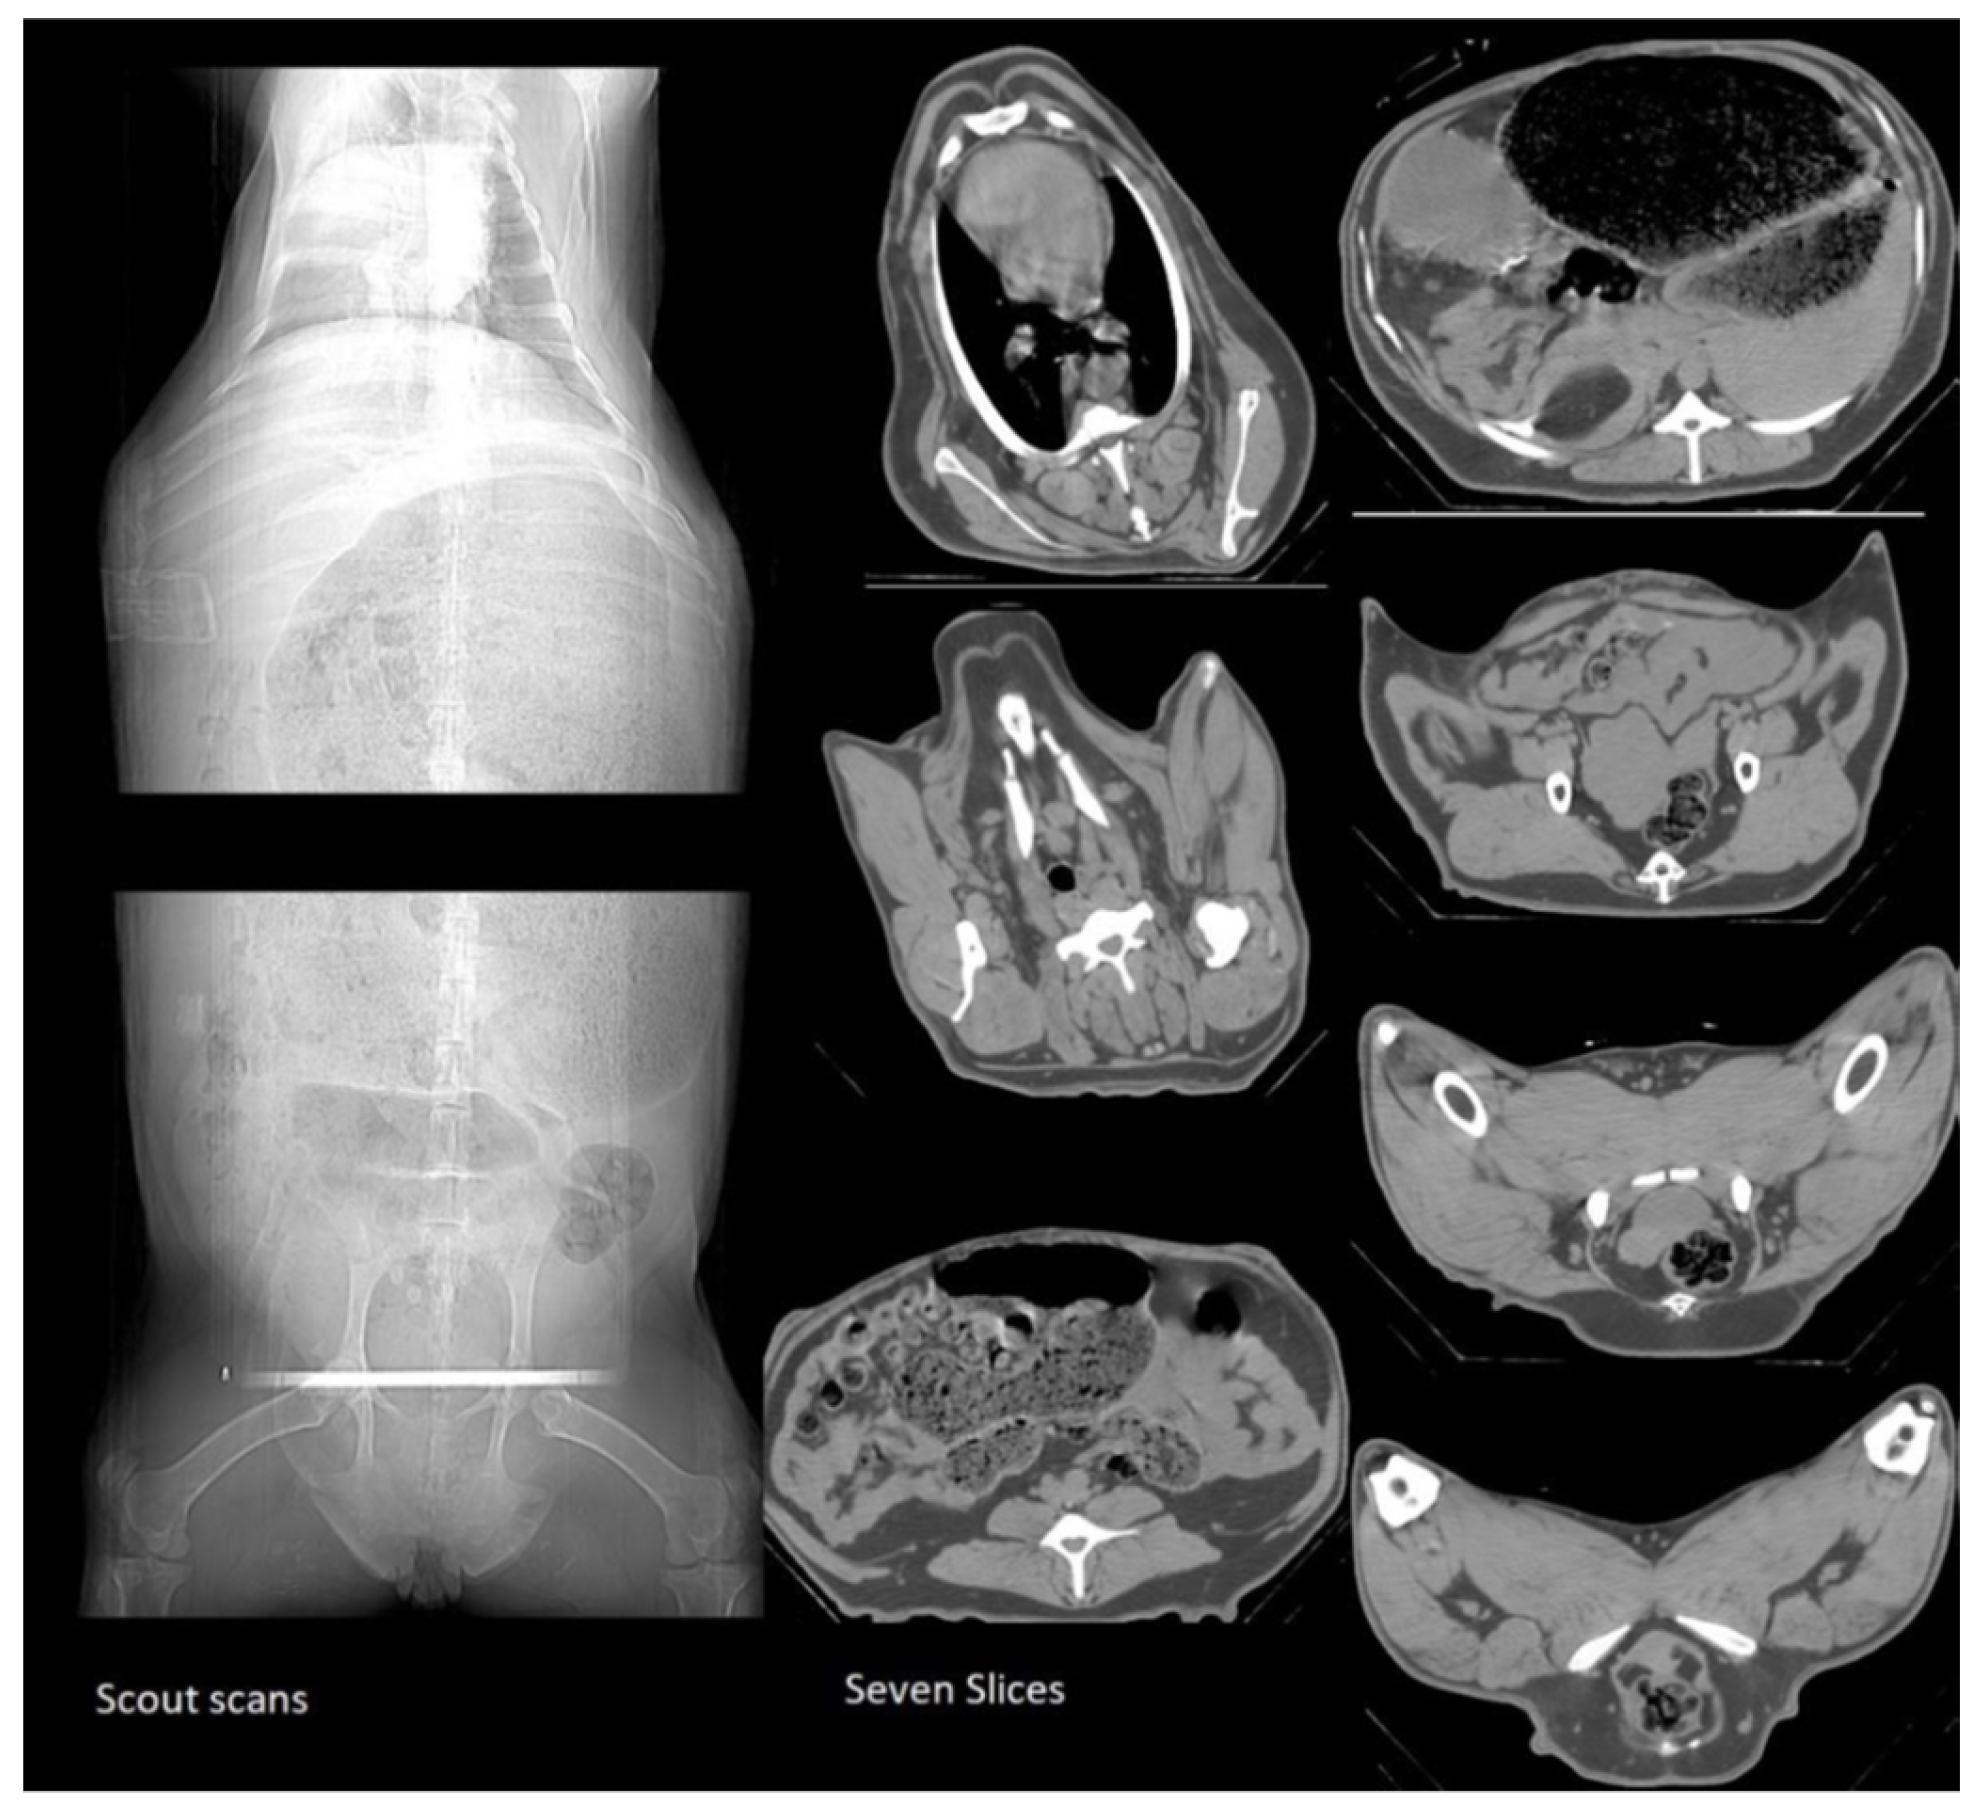

2.2.1. CT scans